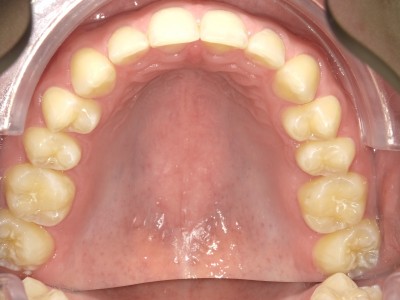

13-24 maand volledig vast onderkaak en bovenkaak + Transforce bovenkaak